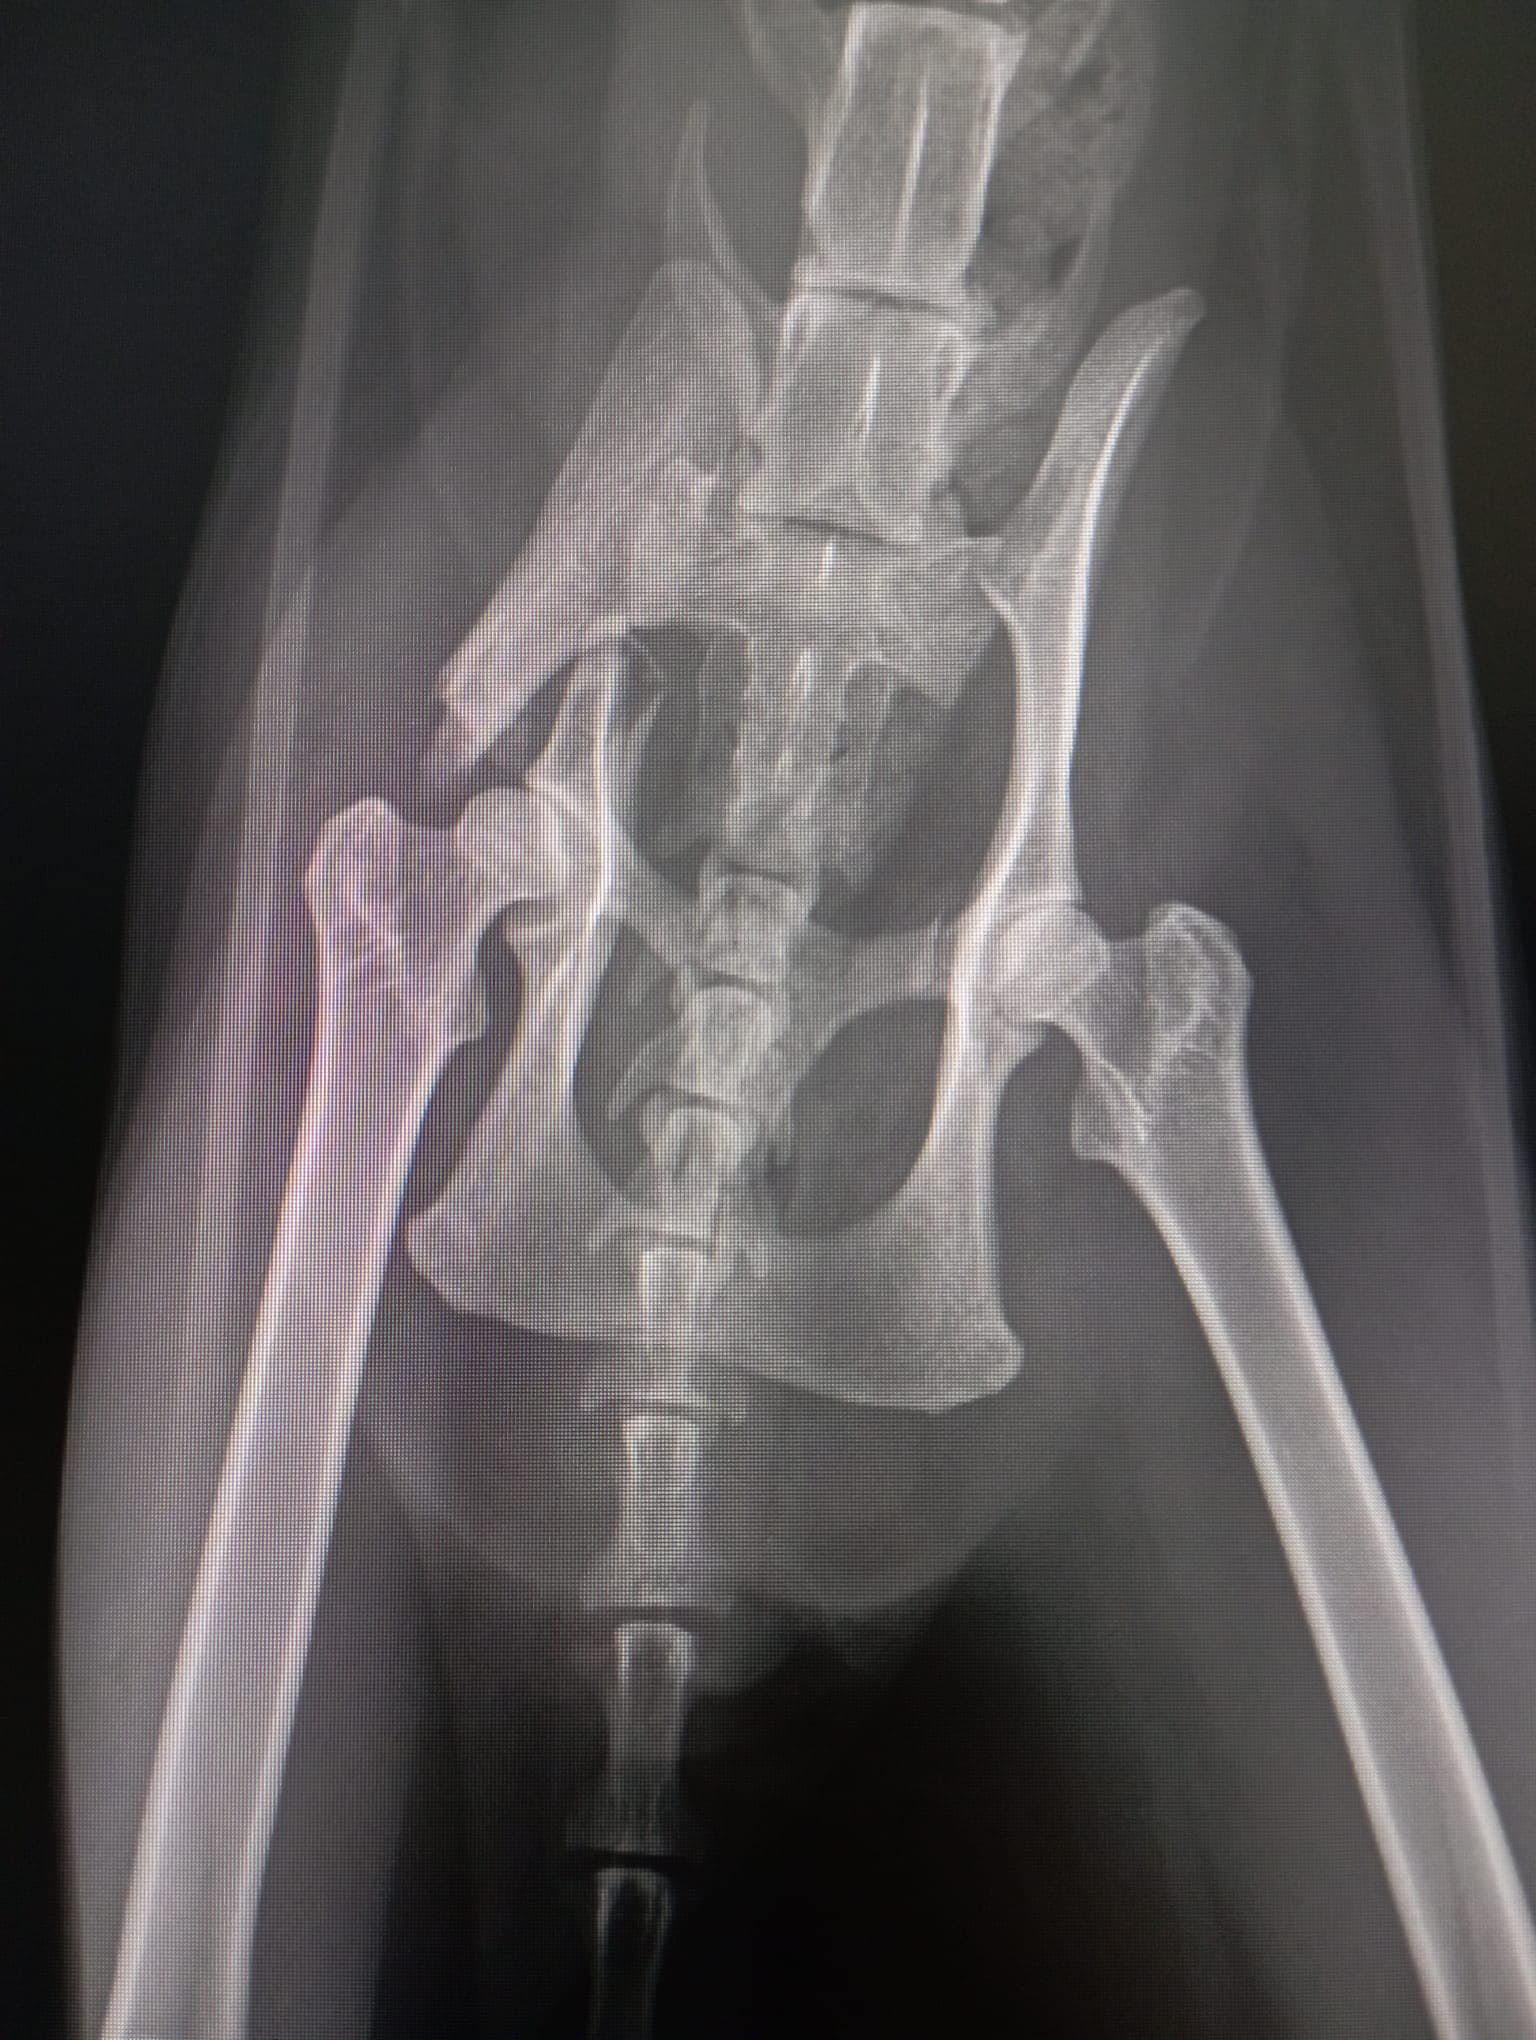

Fratura do olécrano (cotovelo esquerdo) , resultante de um atropelamento recente.

Fratura do íleo (anca direita) , com cerca de 2 a 3 semanas, indicando um segundo atropelamento.

Possível lesão no carpo direito , que pode exigir uma panartrodese no futuro.